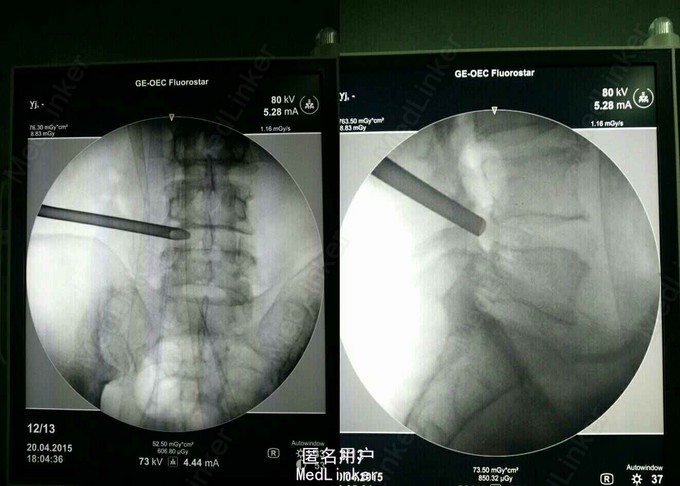

诊断:L45及L5/S1 双节段椎间盘突出(左侧),辅助检查:MRI提示: L45及L5/S1 双节段椎间盘突出,压迫左侧神经根。

术后症状立即缓解,术后两小时佩戴支具下地活动。